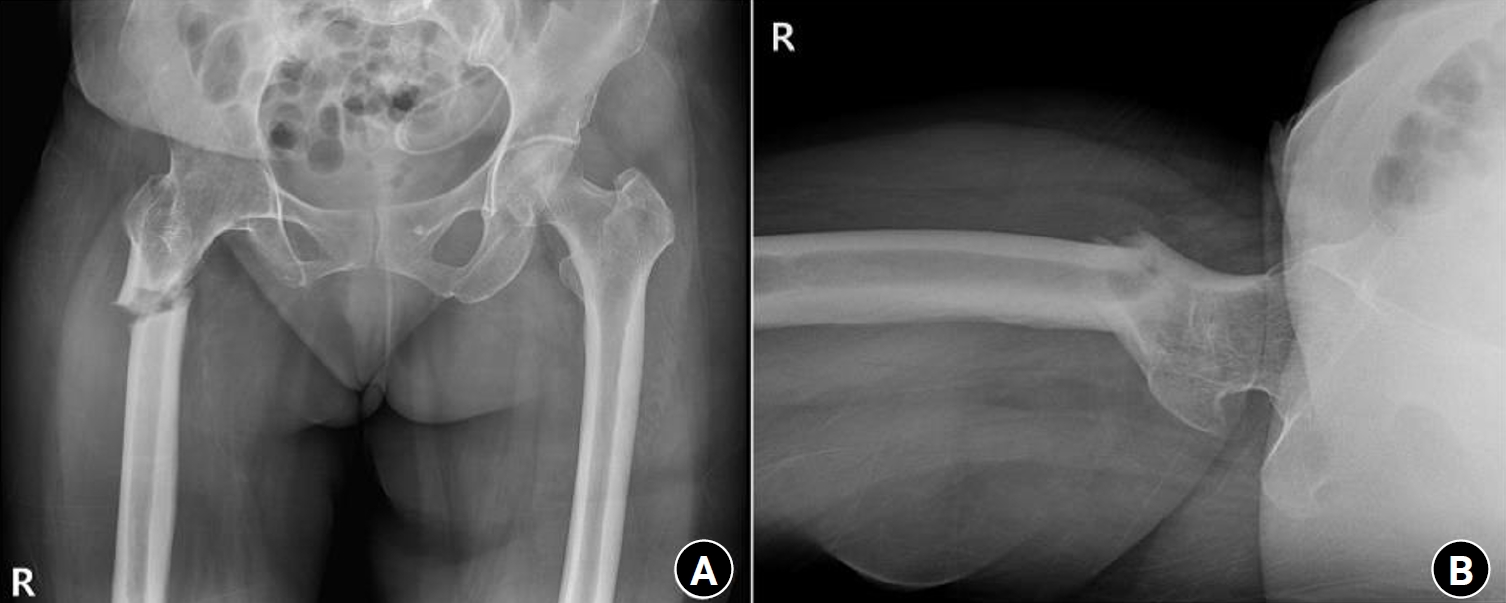

Fig. 3.

Radiographs of the same patient presenting with a right subtrochanteric femoral fracture (Russell-Taylor classification type 1). (A) Anteroposterior view. (B) Axial view.

Fig. 4.

Prefracture radiograph of an 8-year-old female patient who presented with a proximal one-third fracture of the left femur (bilateral lower-extremity standing anteroposterior view).

Case 1: synostosis of hip joint

A 58-year-old female patient visited our emergency room, complaining of pain in the right hip that occurred the day before her hospital visit. She had a history of restricted right hip range of movement following a dislocation of the right hip in her youth, and she typically walked with a cane. The day prior to her visit, while lying on her right side and sleeping, she developed pain in the right hip area without any history of trauma. Upon examination, the patient had a background of hypertension and exhibited a bone mineral density (BMD) of ‒0.1 in the femoral neck. Notably, she had no history of malignancy. Initial physical examination and computed tomography scans conducted upon her arrival did not reveal any signs of malignancy or infection at the fracture site, indicating a low likelihood of these conditions as contributing factors. Radiographic evaluations, including both hip anteroposterior and right axial views, demonstrated signs of synostosis involving the right femoral head and acetabulum. A fracture was observed in the subtrochanteric area of the right femur, characterized by a beak-shaped thickened cortex on the lateral side of the fracture site. Importantly, the radiographs obtained 3 years prior showed no abnormalities at the fracture site (Figs. 2, 3). Following the diagnosis, the patient underwent open reduction and internal fixation using a plate. Subsequent follow-up indicated successful bone union at the fracture site.

Case 2: osteogenesis imperfecta

An 8-year-old female patient visited our emergency room complaining of pain in the left thigh that began on the day of her visit. She slipped and directly injured her thigh upon falling to the left. Initial examination revealed normal laboratory findings, including serum calcium levels of 9.0 mg/dL and inorganic phosphorus levels of 4.7 mg/dL. Radiographic evaluations, including anteroposterior and lateral views of the left femur, demonstrated a transverse irregular fracture line in the proximal one-third area of the left femur, accompanied by lateral cortex hypertrophy. Importantly, the possibility of malignancy or infection as contributing factors to the fracture was considered low. Two years prior, the patient had visited the pediatric department of our hospital due to concerns about her height, which was below that of her peers. Following genetic testing, she was diagnosed with osteogenesis imperfecta and has since been monitored by both the pediatrics and orthopedics departments. At that time, lateral bowing of both femurs was observed in both lower extremities during standing anteroposterior evaluations (Figs. 4, 5). She had previously undergone epiphysiodesis on both femurs due to genu valgum. After diagnosis, the patient underwent open reduction and internal fixation using an ender nail. Follow-up evaluations indicated successful bone union at the fracture site.